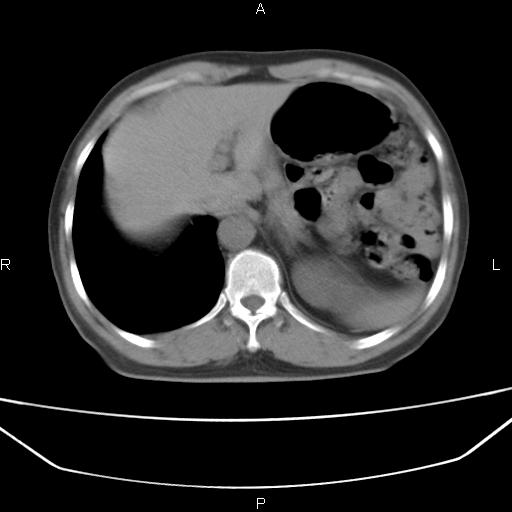

患者,男。50岁。近几日有咳嗽症状,无其他不适,既往病史无,考虑膈疝。请前辈们看看指导指导。

膈膨升,左下肺通气不良,膈肌好像还完整。

考虑左侧膈疝。

左侧膈疝。

符合隔膨升,膈肌较完整。